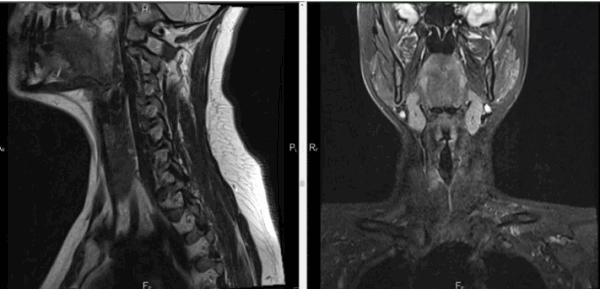

МРТ мягких тканей шеи что показывает

Воспалительные заболевания и объемные образования шеи часто встречаются в хирургической практике. Дифференциация патологий вызывает трудности из-за сложной анатомии рассматриваемой области и схожести клинических проявлений. МРТ позволяет получить подробные изображения мягкотканных и костных структур, опираясь на принцип магнитного резонанса. Компьютерная программа преобразует данные в серию срезов и формирует объемную картинку, которую можно увеличивать и рассматривать в любой плоскости. Толщину среза устанавливает врач в зависимости от предполагаемого диагноза, целей и задач исследования.

Магнитно-резонансная томография указанной области, вариант нормы

Что входит в МРТ мягких тканей шеи?

Патологический процесс в указанной области может затрагивать:

жировую и соединительнотканную клетчатку;

поверхностные и глубокие лимфатические узлы;

гортань, надгортанник, щитовидную железу, пищевод, трахею;

часть позвоночного столба со спинным мозгом и пр.

В норме МРТ мягких тканей шейного отдела не визуализирует паращитовидные железы, если последние присутствуют на МР-сканах, речь идет об аденоме.

Анатомия шеи

Внутренние структуры зоны интереса

Анатомическая область включает межфасциальные пространства:

пред- и позадиорганное;

Наибольший интерес представляет висцеральное пространство, включающее органы шеи:

глотку с верхней частью пищевода;

гортань и трахею;

пара- и щитовидную железы;

возвратный гортанный нерв.